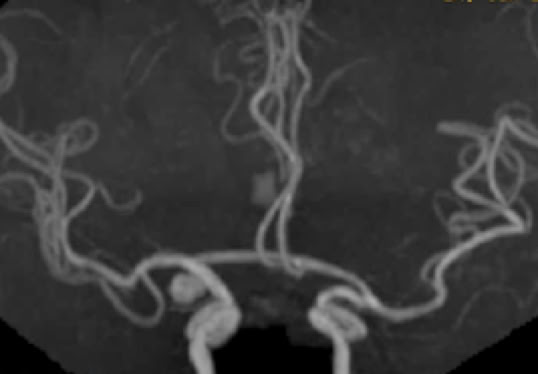

3. 脳MRA:MRIによる脳血管の撮影です.脳動脈瘤(脳の動脈にできるコブ),動脈狭窄(細くなる)・閉塞(つまってしまう)などを検索します.

脳動脈瘤のMRA画像

脳MRA(脳動脈瘤)